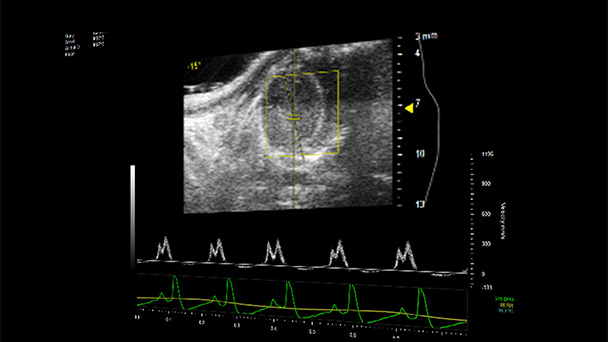

Scientists at the Miller School of Medicine have developed a model that replicates heart failure with preserved ejection fraction, which has very limited treatment options. The authors believe this new model will boost exploration and expand therapeutic choices for patients.